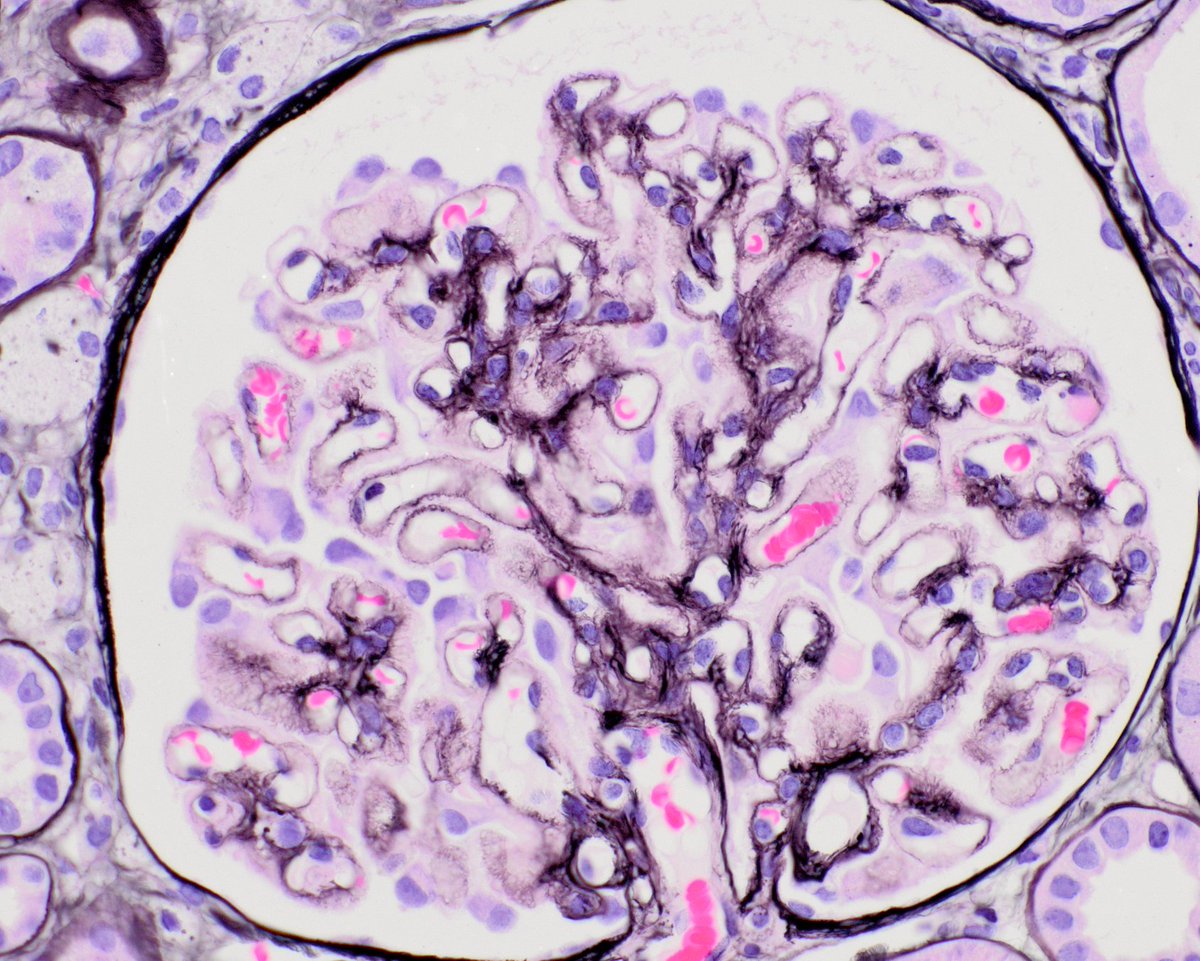

A simple classic case, because if you need to know something for path and nephrology boards in renal path, you need to know about PLA2R positive membranous. It was a game changer. For patient care too. It all started here nejm.org/doi/full/10.10…

MessiasNidia's tweet image. A simple classic case, because if you need to know something for path and nephrology boards in renal path, you need to know about PLA2R positive membranous. It was a game changer. For patient care too.  It all started here nejm.org/doi/full/10.10…